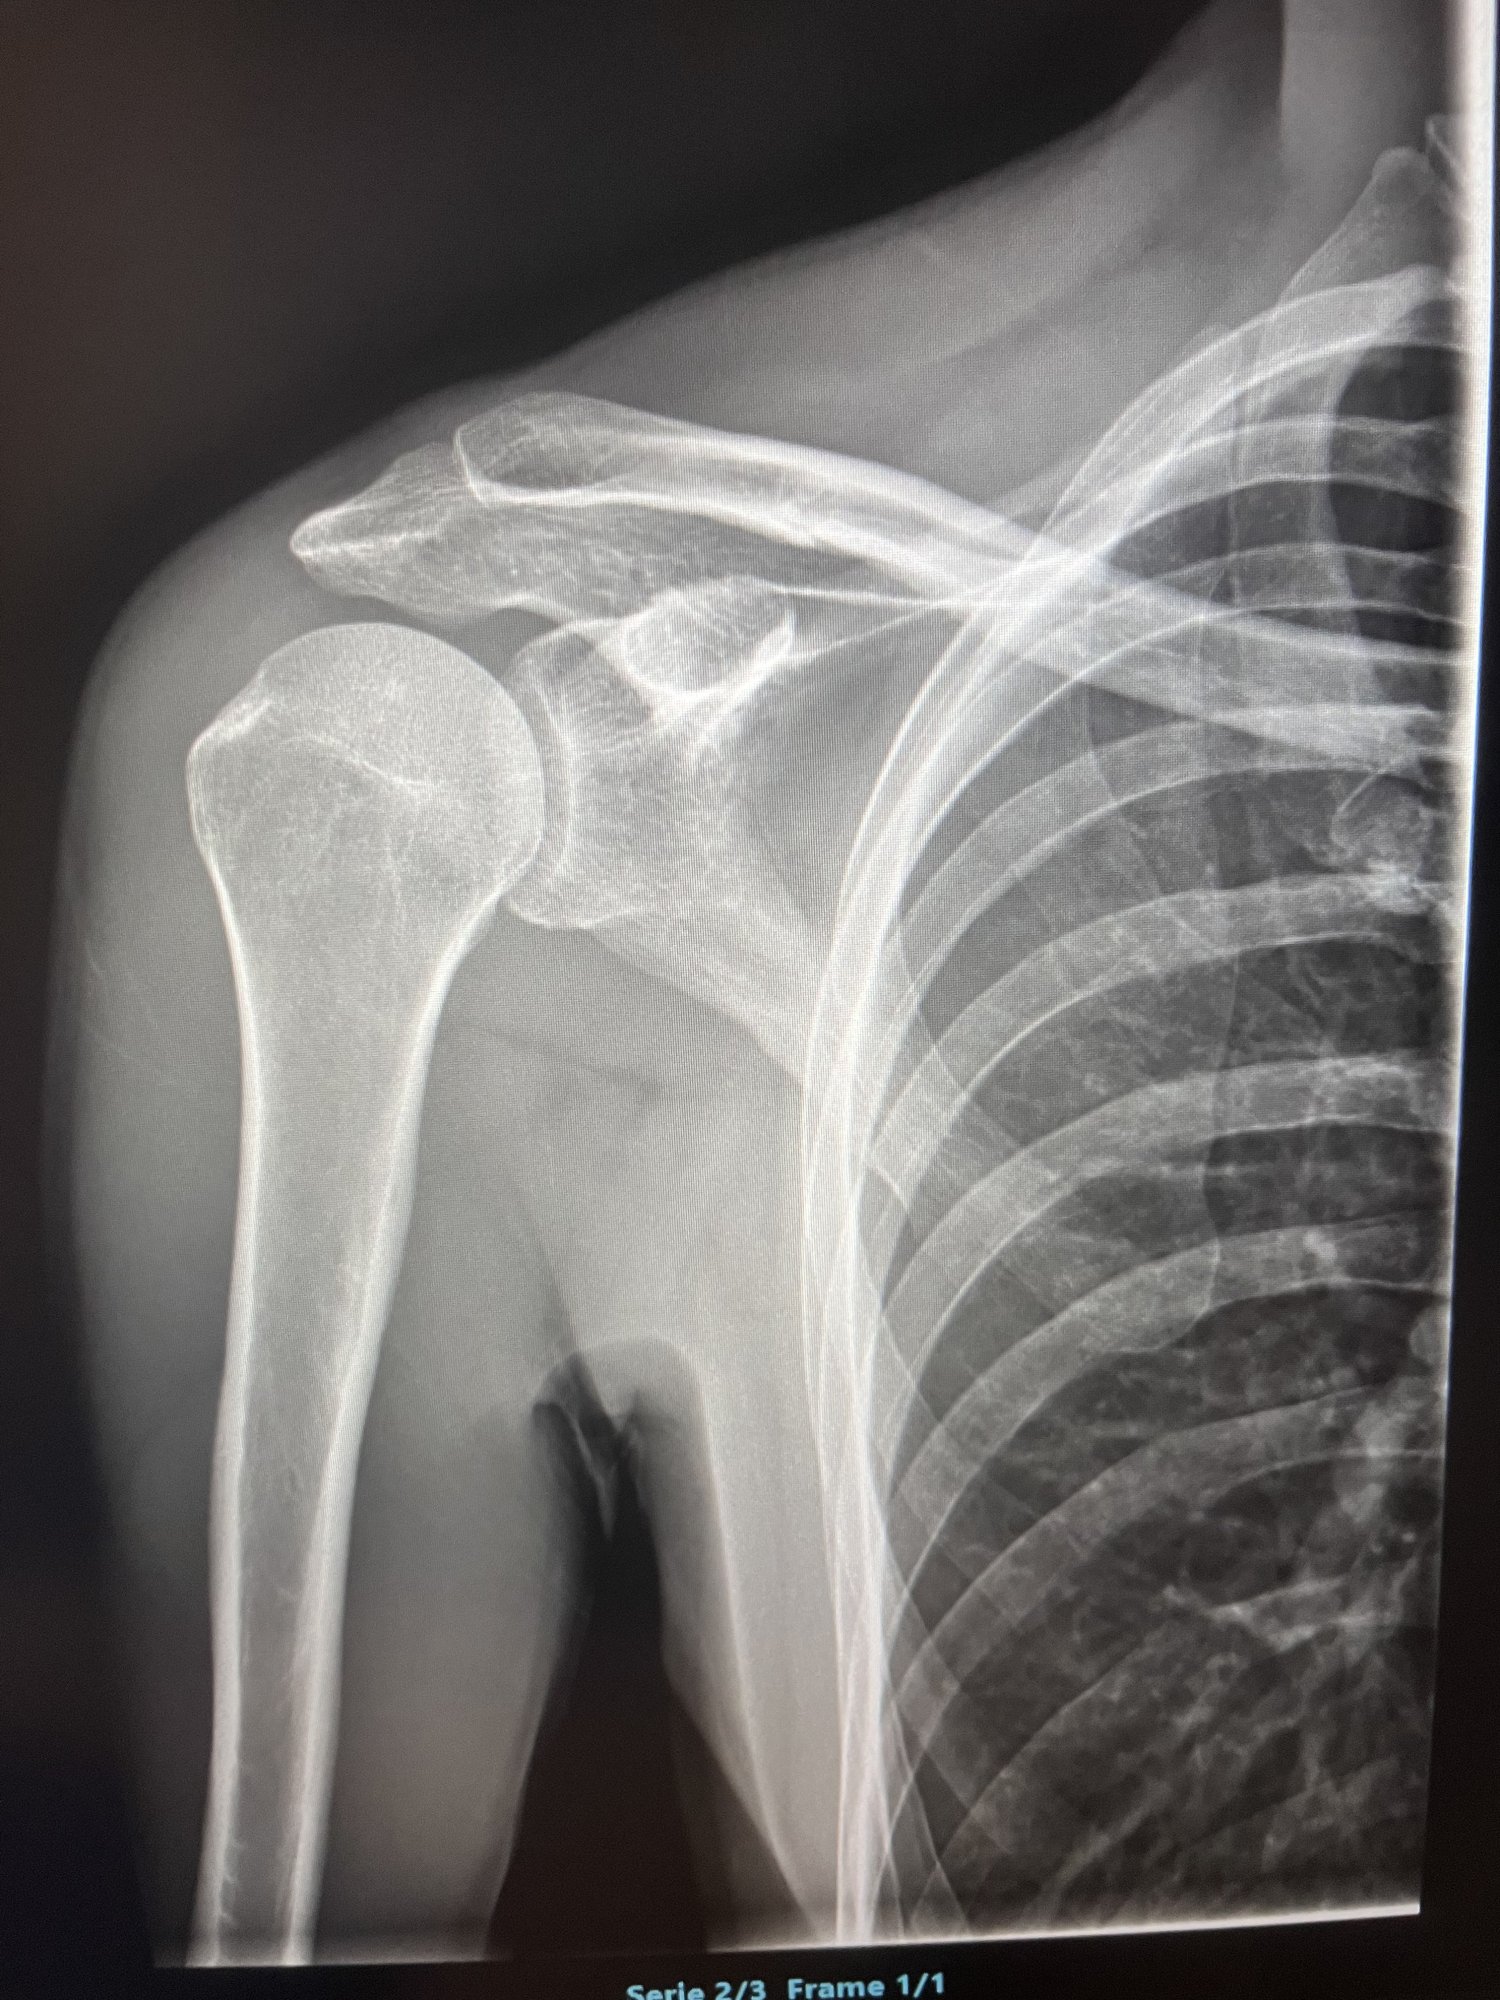

Antrag Mitgliedschaft im Fan-Club:

Bei einem der harmlosesten Stürze in den letzten 30 Jahren passiert. Einfach nicht aufgepasst, in eine Strassenbahnschiene geraten und abgeworfen worden.

Ich bin laut Spuren auf dem Trikot, primär ungefähr Mitte Schulterblatt mit dem Rücken auf dem Asphalt aufgeschlagen.

Das hat dann zu folgendem geführt:

Das war vor 6 Wochen, 5 Tage später kam ne Platte mit 6 Schrauben rein.

Nächste Woche geht es zwecks Kontrolle zum Röntgen.

Aktuell habe ich zweimal die Woche Physio und die Ansage den linken Arm nicht zu belasten und auf keinen Fall über 90° zu gehen.